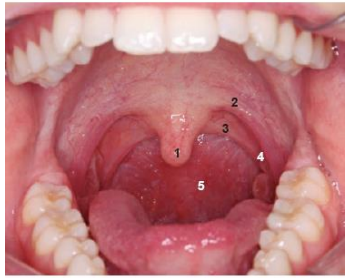

O palato mole contém músculos e tecido fibroso revestidos por mucosa. Durante a deglutição, o palato mole se eleva, evitando a entrada de alimento na parte nasal da faringe. Na fonação, ele pode elevar-se mais ou menos, causando um velamento total ou parcial da boca em relação à parte nasal da faringe, a depender do tipo de som emitido (som nasal ou vocálico)

Levando em consideração a estrutura bucal, analise a imagem e estabeleça a relação com a denominação e número:

A sequência CORRETA é:

1. Úvula.

2. Arco palatoglosso.

3. Arco palatofaríngeo.

4. Tonsila palatina na fossa tonsilar.

5. Parte oral da faringe.